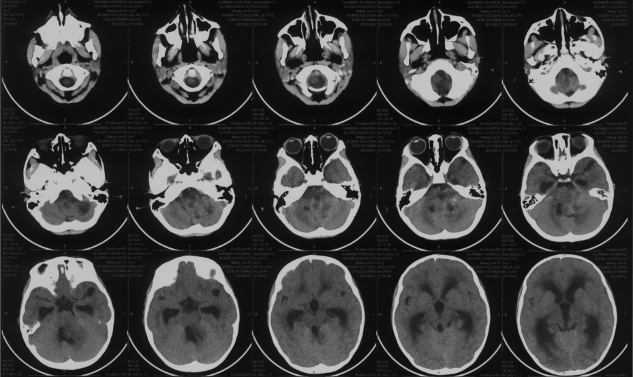

Preoperative CT